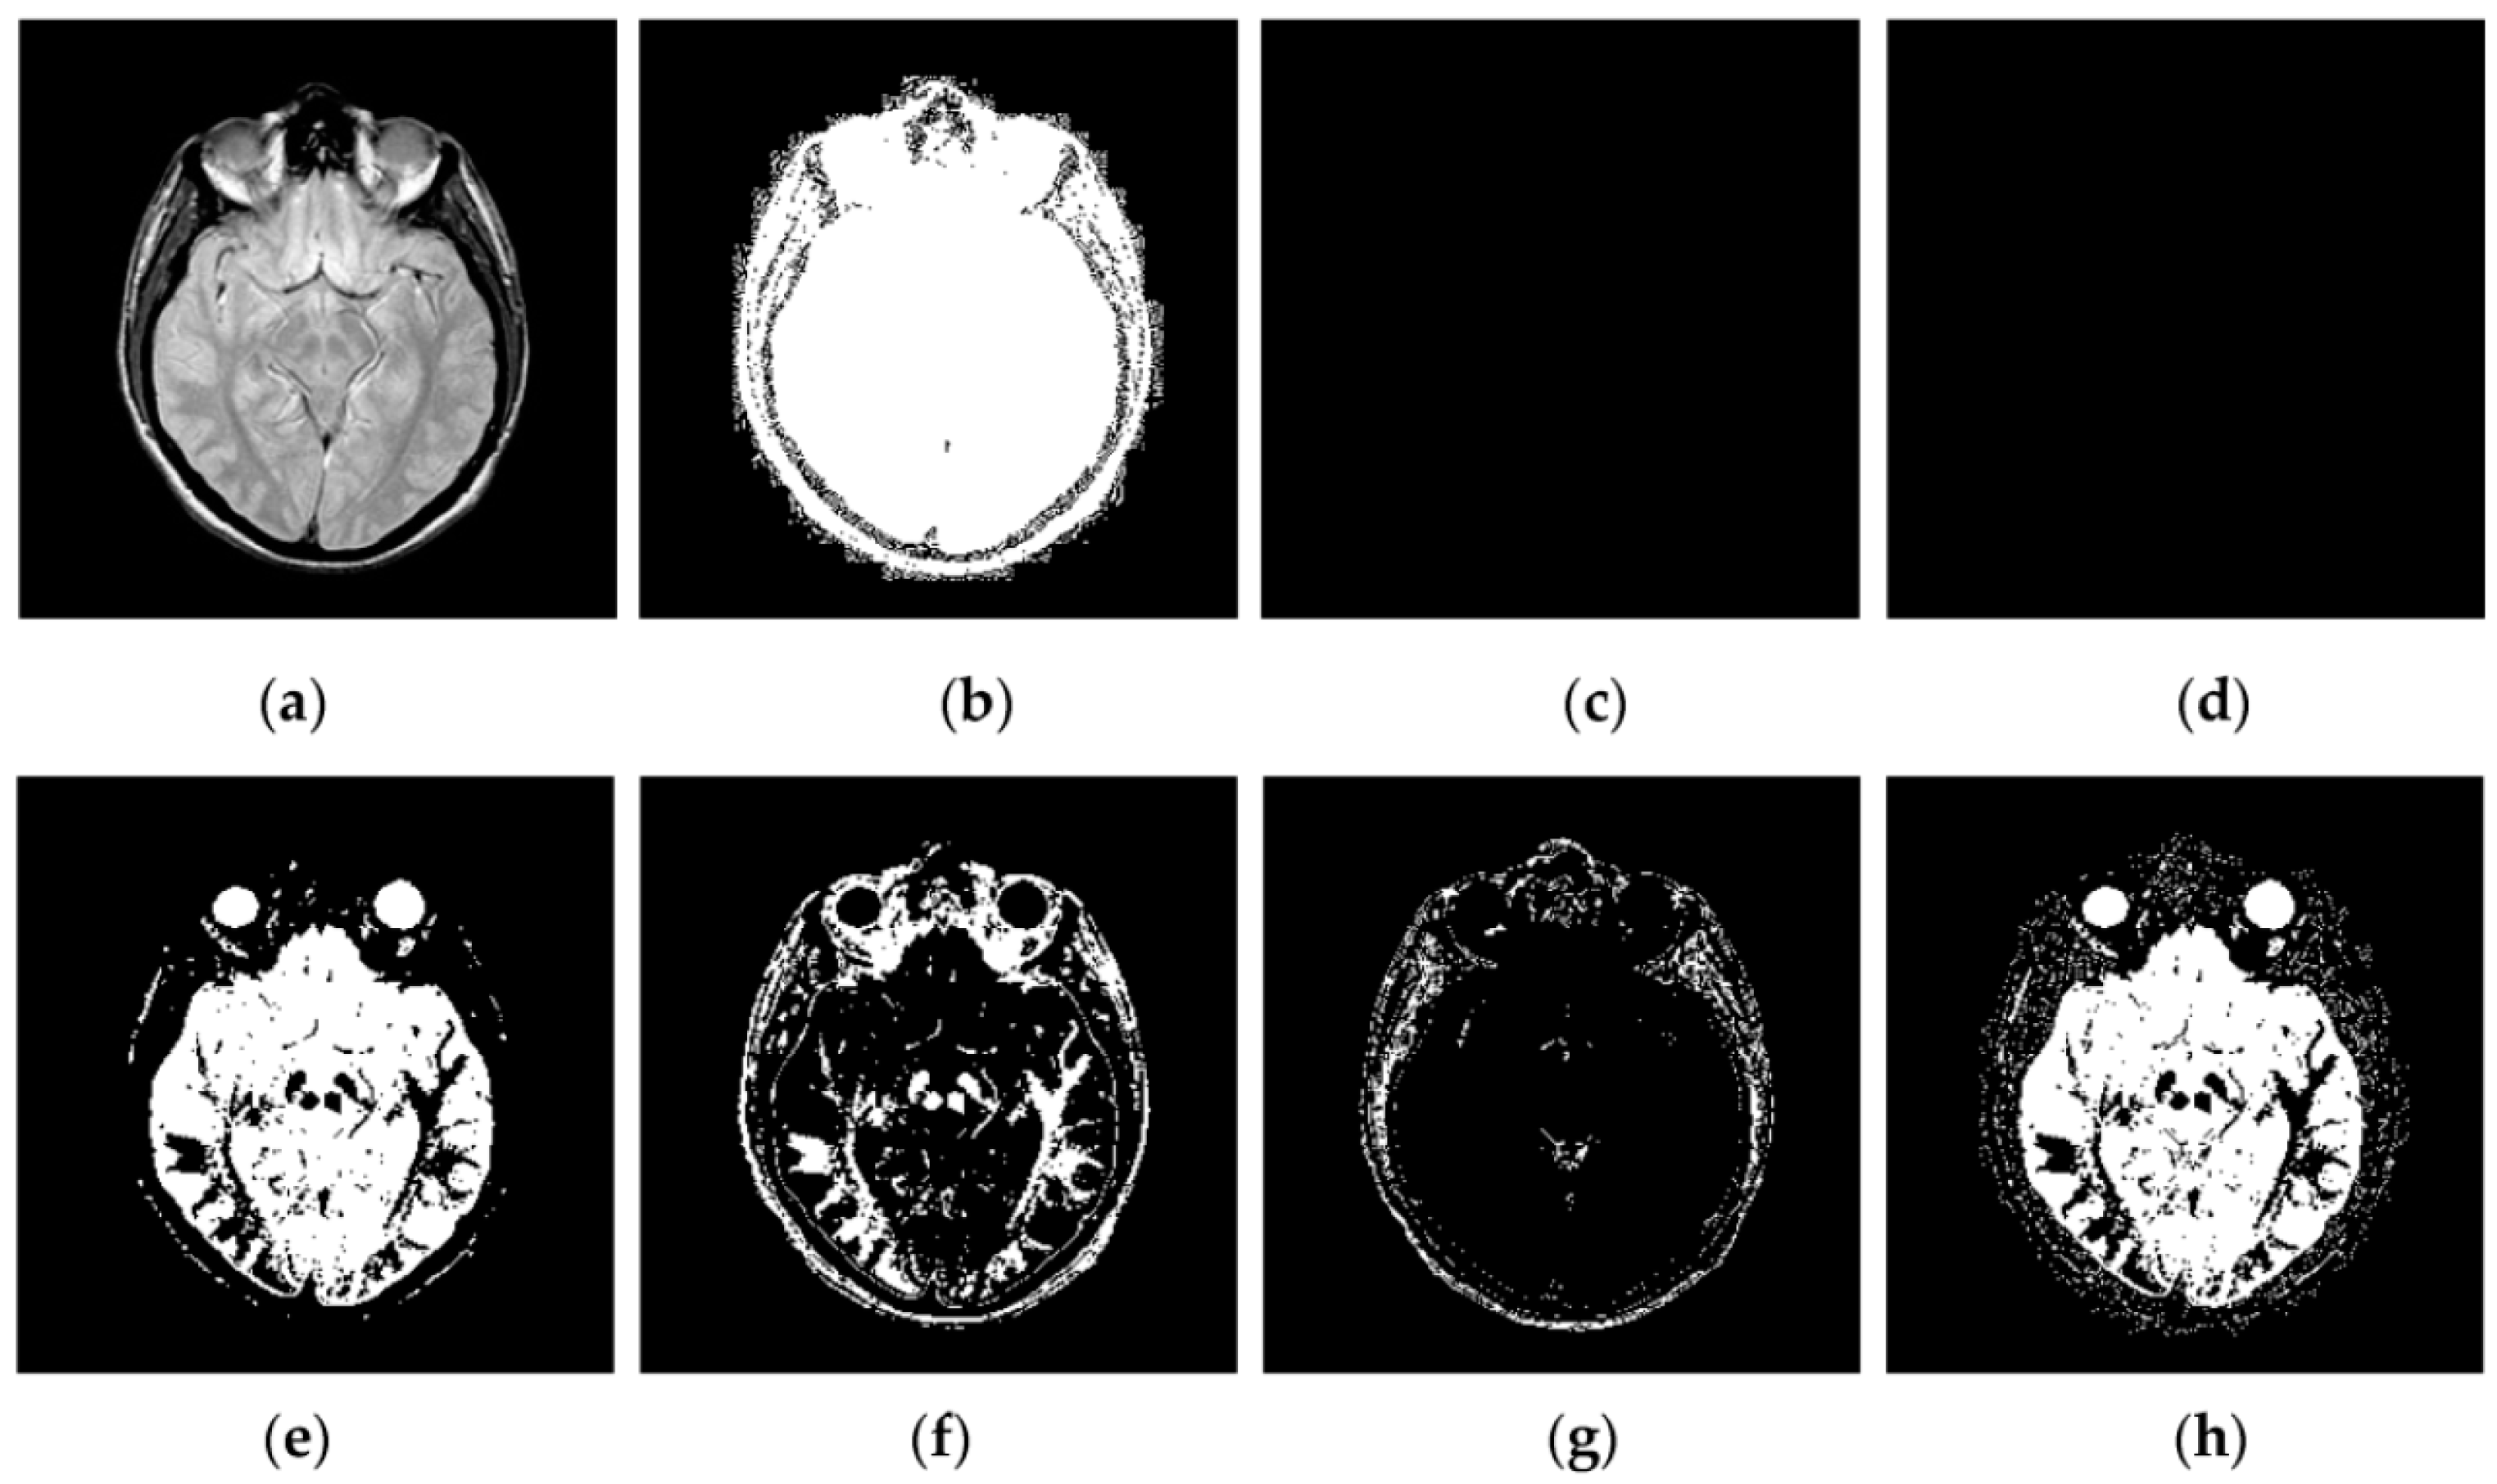

Through iterative computation, the SCM neurons output the temporal series of binary pulse images. The temporal series contain much useful information of input images. To explain this point better, Figure 2 shows the temporal series produced by the SCM with f = 0.9, g = 0.3, h = 20 and Nmax = 7 operating on an input MR image shown in Figure 2a. In Figure 2, we can see that during the various iterations, the output binary images contain different image information and the outputs of the SCM typically represent such important information as the segments and edges of the input image. The observation from Figure 2 indicates that the SCM can describe human visual perception. Therefore, the pulse outputs of the SCM can be utilized for image fusion.

Figure 2.

Temporal series of pulse outputs generated by the SCM operating on magnetic resonance (MR) image: (a) MR image; and (b–h) the binary pulse images from the first to the seventh iteration, respectively.